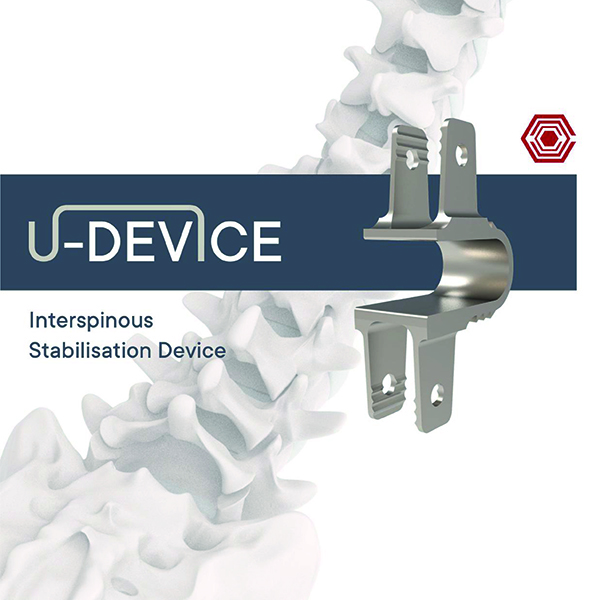

U-Device

Akif Kaya Aybek

Norm Akademi

- Surgical Technique

- Implant Sizes

- Instrument Container

- Instrument Types